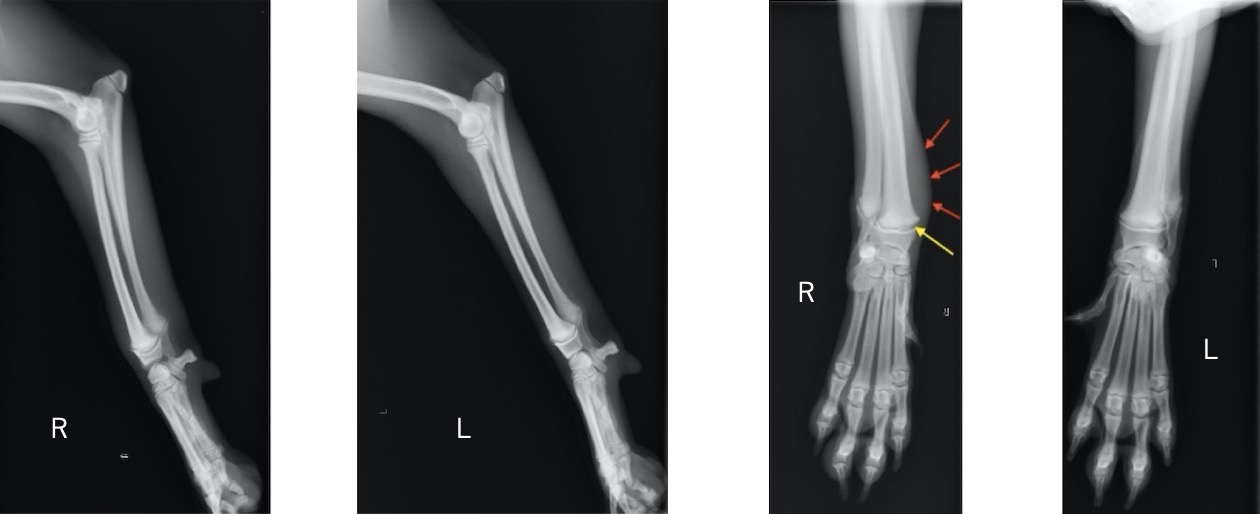

単純X線画像検査上、ラテラル像では大きな左右差は認められませんでしたが、AP像にて軟部組織の腫脹と成長板の間隙が広くなっていることから橈骨遠位成長板骨折(Salter-Haris Type1)と診断し、外科的処置を行いました。

初心時のX線画像検査初見 赤矢印:軟部組織の主張、黄矢印:橈骨遠位成長板(左前肢と比較すると成長板の間隙が広い)